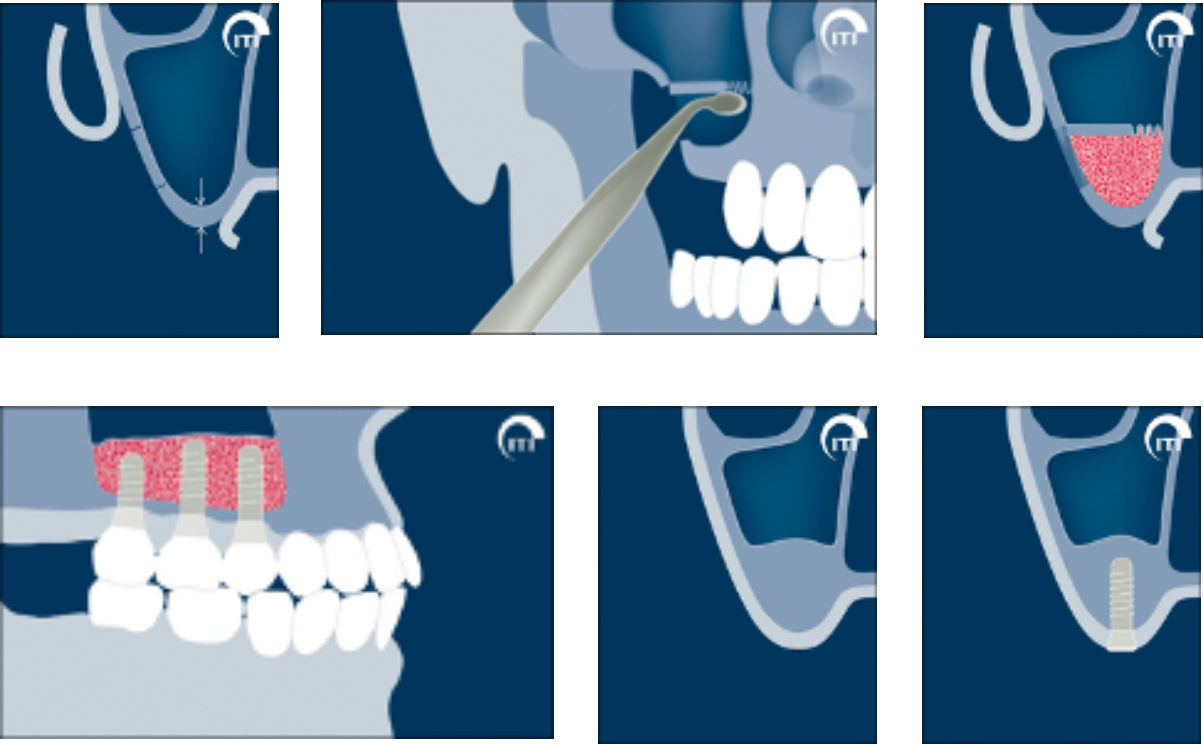

骨の形によっては、インプラントを埋入すると一部が口の中に露出することがあります。露出した部分をそのままにすると細菌が集まり、骨が吸収する原因となるので、露出した部分には人工骨などで覆い骨を作ります。先に人工骨で骨を作り、しっかりと骨ができた段階でインプラントを埋入することもあります。

インプラントを埋入すると部分的に露出したので人工骨で覆いました。